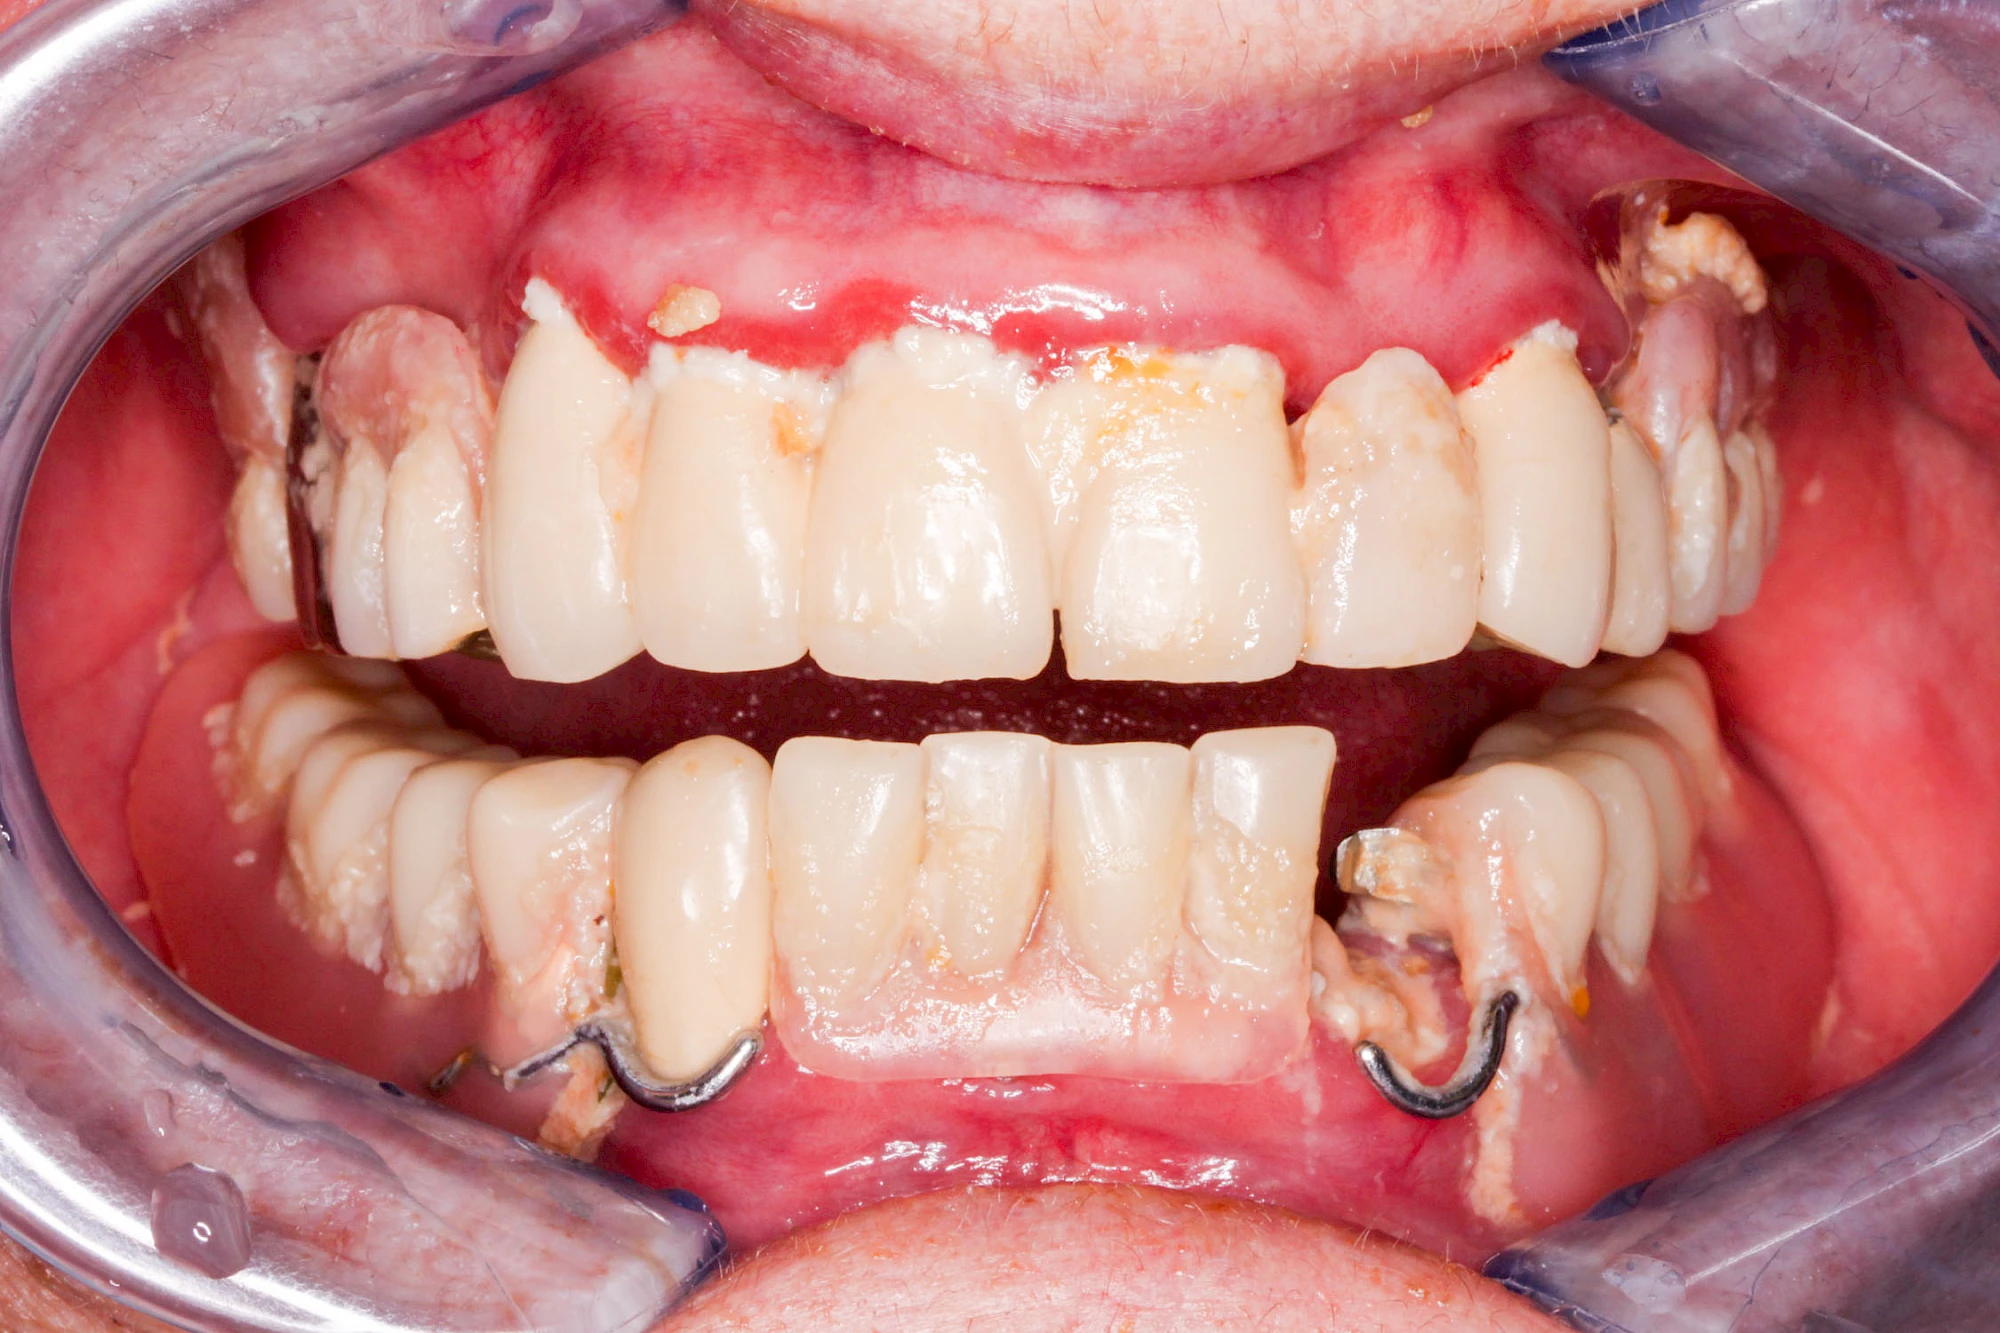

Bei Implantaten – also operativ eingebrachten künstlichen Zahnwurzeln – kann der Körper die Bakterien auch nicht so gut abwehren. Hier spricht man im Fall einer Entzündung von einer Peri-Implantitis, also einer Entzündung um das Implantat herum.

Diese Vermehrung von Bindegewebe in einem frei gewordenen Raum ist eine Sonderform der Anpassungsreaktion menschlicher Zellen und wird als Vakatwucherung bezeichnet.

Früher wurden im Unterkiefer mitunter Brücken zum Ersatz fehlender Zähne als sogenannte "Schwebebrücken" gestaltet. Die Idee dabei war, dass man die Brücke insgesamt besser reinigen kann. Allerdings war das für die Patienten mitunter irritierend für die Zunge und vor allem beim Essen gewöhnungsbedürftig. Teilweise haben sich hier reaktiv Vakatwucherungen der Kieferkammschleimhaut gebildet und den Raum unter der Brücke wieder verschlossen.